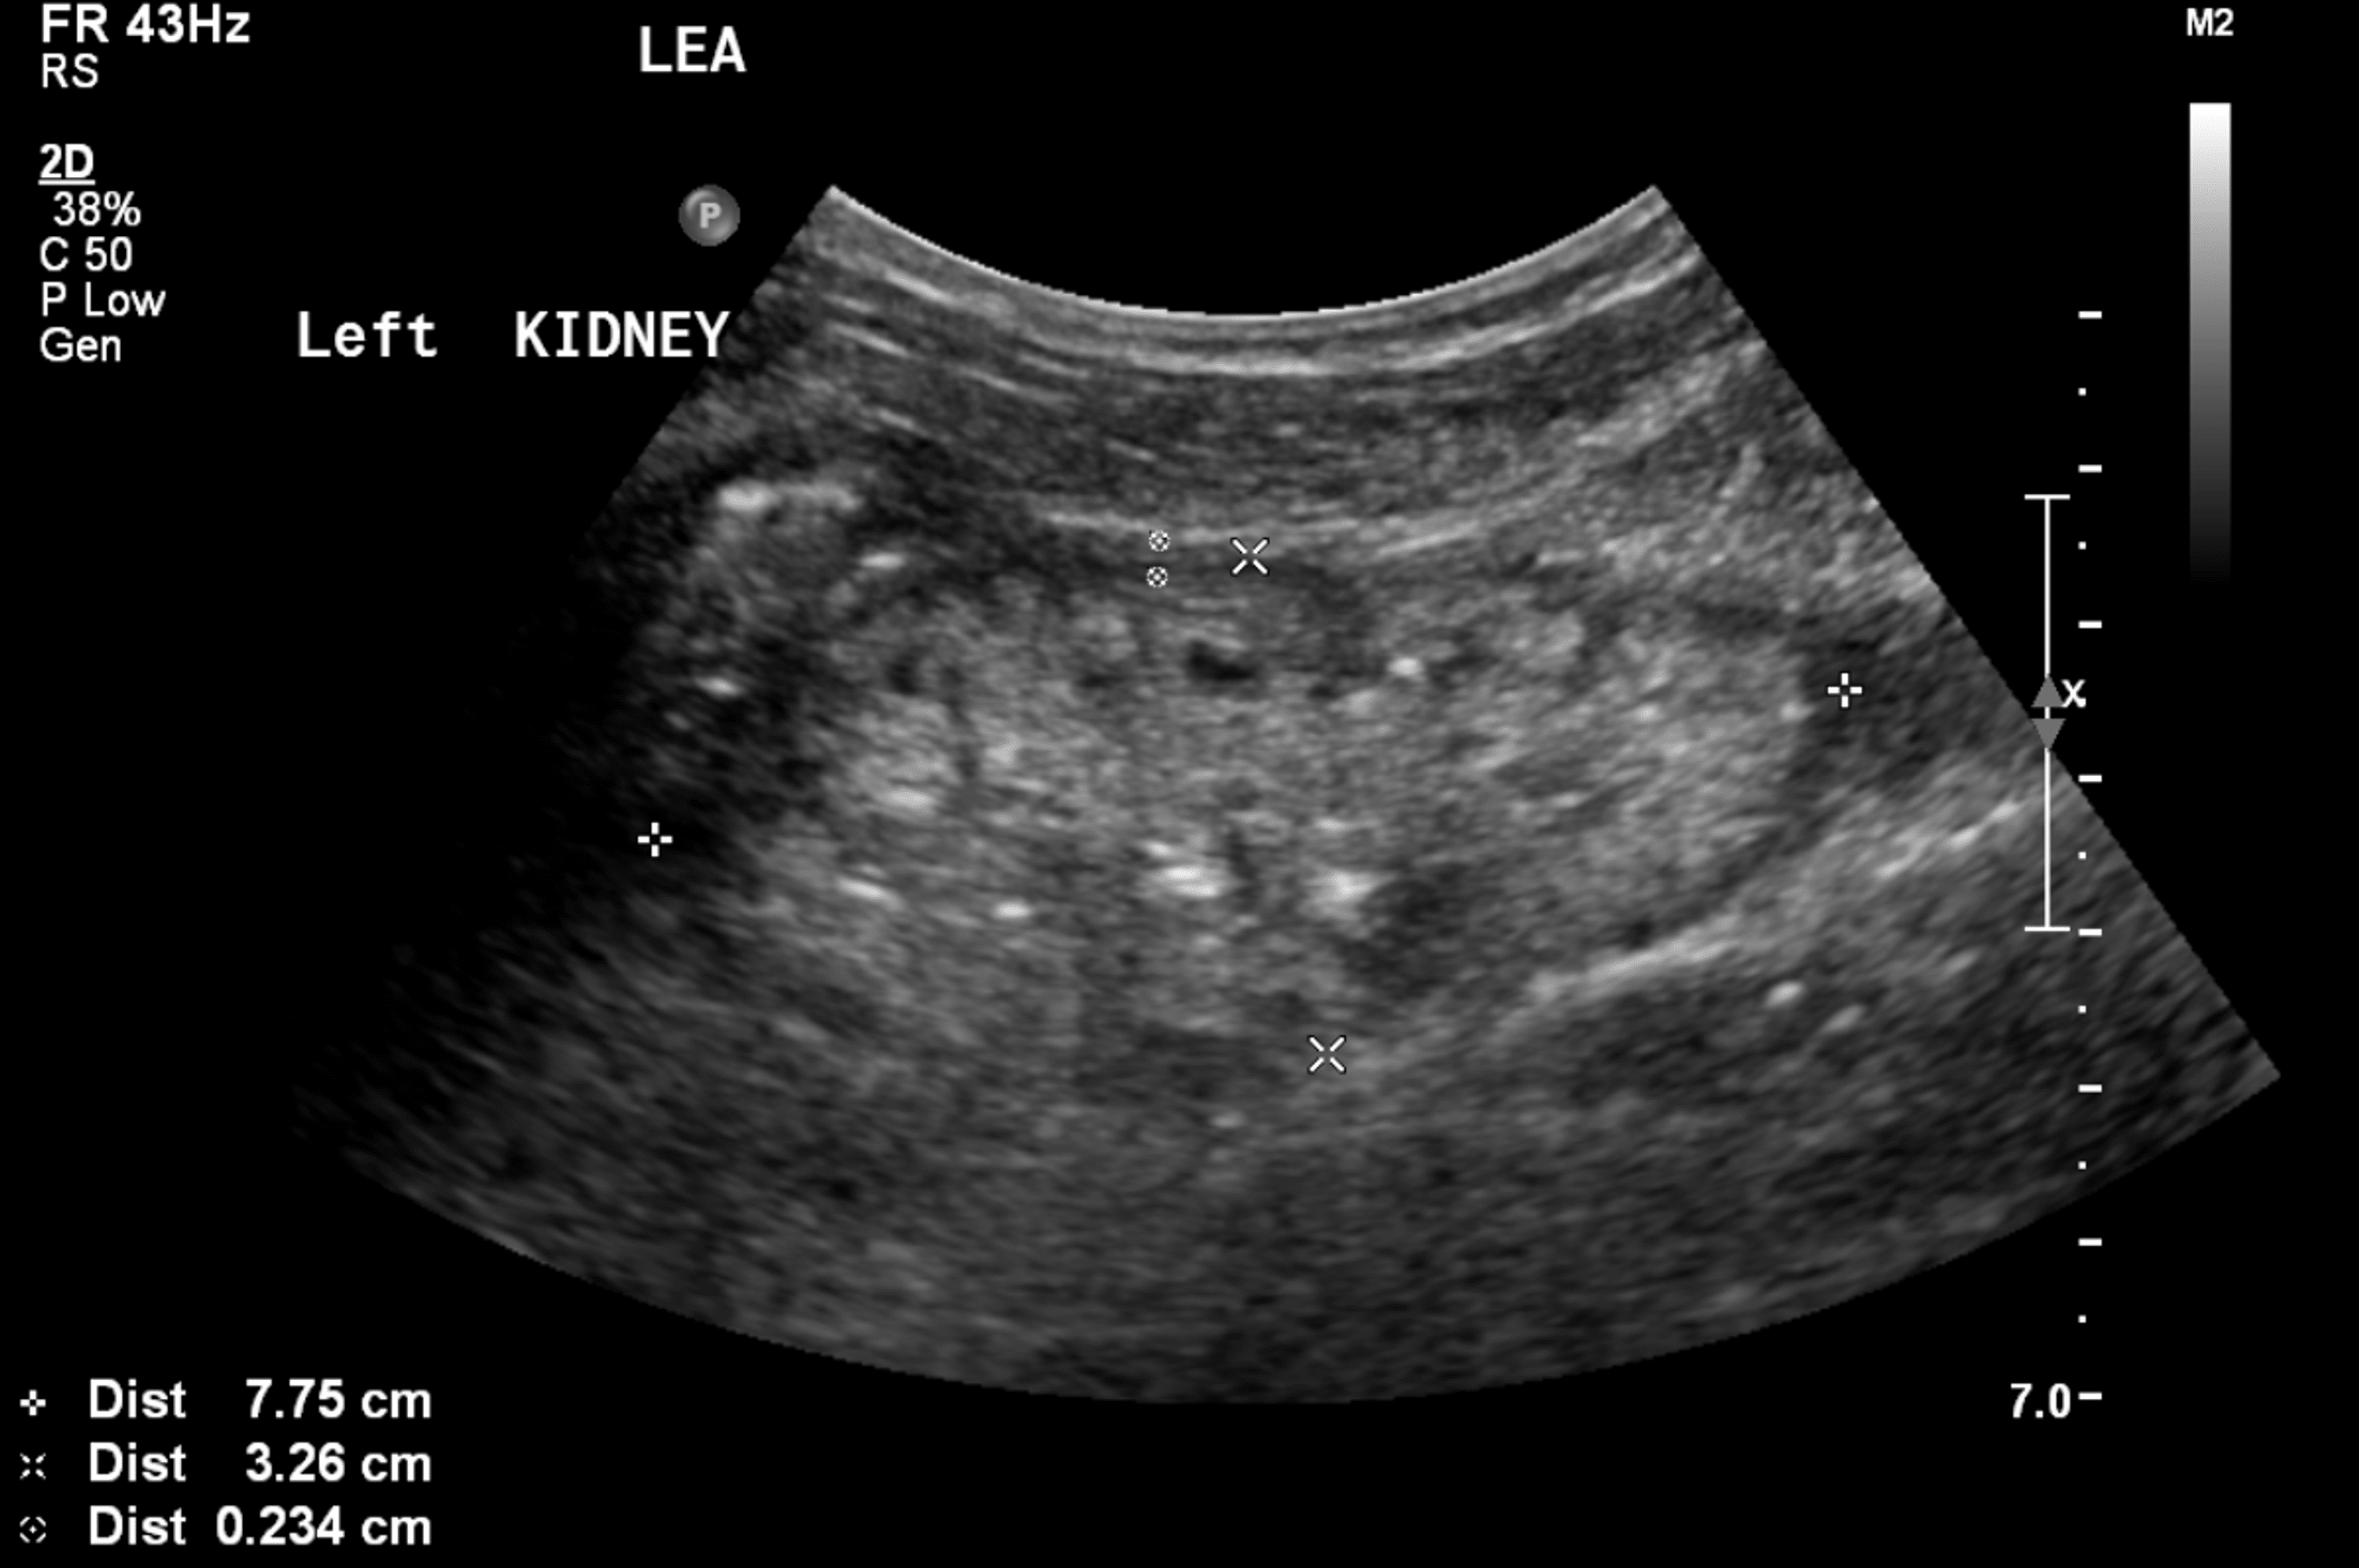

Kidney ultrasound in a patient with TBMD, proteinuria and CKD, showing Proteinuria Kidney Ultrasound Sometimes, to make a firm diagnosis of the cause of. Urine albumin measurement is an important component in screening for chronic kidney disease. It is vital for those at risk of heart disease, diabetes, raised blood. Quantifies the amount of proteinuria compared to creatinine excretion; The presence of proteinuria is an. Repeat tests are more reliable for detecting renal pathology. Proteinuria Kidney Ultrasound.

Kidney ultrasound in a patient with TBMD, proteinuria and CKD, showing Proteinuria Kidney Ultrasound If the acr is 70 mg/mmol or more, protein:creatinine ratio (pcr) can be used as an alternative to acr. Urine albumin measurement is an important component in screening for chronic kidney disease. The size and shape of the kidneys may be measured with an ultrasound (sound wave) scan. The presence of proteinuria is an. Quantifies the amount of proteinuria compared. Proteinuria Kidney Ultrasound.

Kidney ultrasound in a patient with TBMD, proteinuria and CKD, showing Proteinuria Kidney Ultrasound It is vital for those at risk of heart disease, diabetes, raised blood. Repeat tests are more reliable for detecting renal pathology as they reduce the likelihood of transient proteinuria from exercise,. The size and shape of the kidneys may be measured with an ultrasound (sound wave) scan. Quantifies the amount of proteinuria compared to creatinine excretion; Albuminuria (proteinuria) is. Proteinuria Kidney Ultrasound.